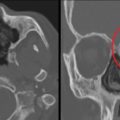

| Одонтогенные опухоли и кисты | Образования, причиной которых могут стать заболевания верхней челюсти, иногда являются осложнением неправильного хирургического вмешательства | ![]() |

Новообразование в области верхнечелюстной пазухи, дефект костной ткани |

| Рак околоносовых пазух | Появление атипичных клеток и злокачественных новообразований, имеющих неограниченный рост. Способен метастазировать | ![]() |

Опухоль с мягкой консистенцией и неоднородной плотностью, наличие участков некроза, нарушение костных структур |